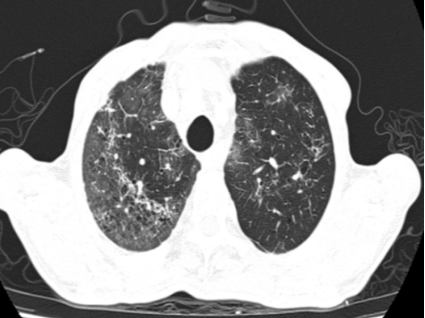

患者王大爷因“咳嗽、胸闷3天,呼吸困难加重5小时”被120紧急送入本部院区就诊。入院时患者高热、呼吸极度困难,肺部听诊可闻广泛Velcro啰音,血气分析提示Ⅰ型呼吸衰竭,胸部CT显示双肺弥漫性结节斑片影。患者有溃疡性结肠炎病史,曾使用激素治疗,初步诊断为重症肺炎。病情危急,医疗团队立即予以高流量氧疗、抗感染及激素治疗,并由贾兆广副主任医师行床旁气管镜检查,送检支气管灌洗液进行tNGS病原学检测。

胸部CT:双肺弥漫结节斑片影